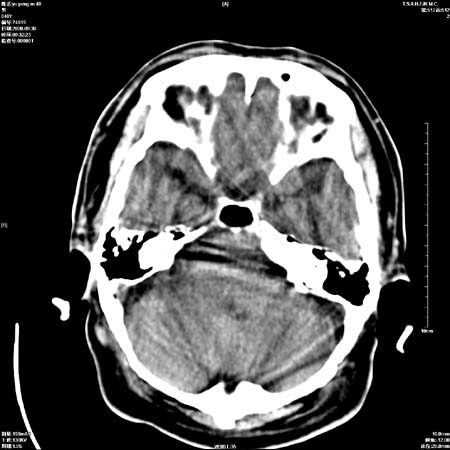

以下是引用zjzjr在2008-10-4 20:29:00的发言:[br]右颞叶皮质区密度略减低,脑沟较对侧变浅,考虑早期脑梗塞,建议mri.左侧小脑幕缘旁可见带状低密度影,轻度占位效应,支持蛛网膜囊肿,枕大池区亦考虑蛛网膜囊肿.